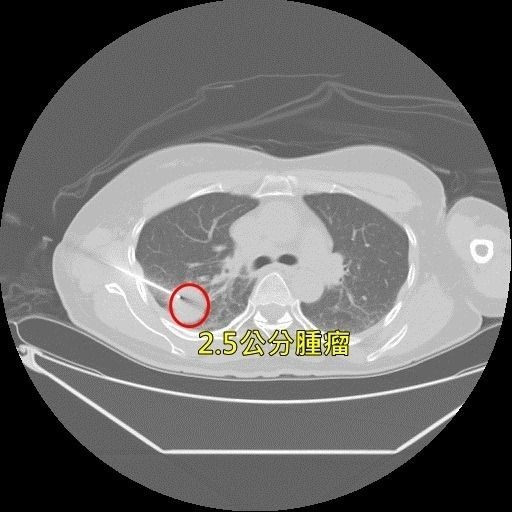

健檢查出「肺結節」不理 一年後成肺癌